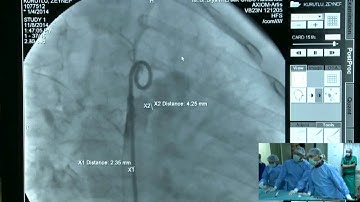

Nit-Occlud® Coil System for PDA Closure